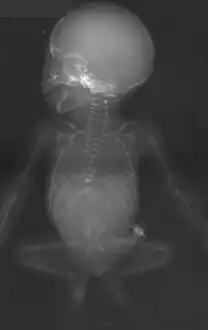

- Antero-posterior radiographic view, showing missing ribs, absent lumbosacral vertebrae, hypoplastic pelvis and "frog-like" position of the lower extremities